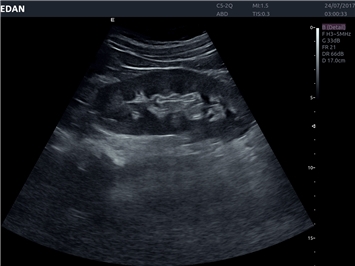

Система Acclarix LX4 оптимально подходит для:

• Общей визуализации

EDAN Acclarix LX4 представляет собой инновационную ультразвуковую систему, построенную на усовершенствованной платформе Acclarix. Сочетание высокого качества визуализации с интеллектуальным рабочим процессом делает эту систему оптимальным выбором для клиник, ценящих эффективность и экономичность.

• Запатентованная технология адаптивной визуализации тканей

• Функция eSRI для подавления зернистости изображения

B-режим, Двухмерное сканирование:

Да